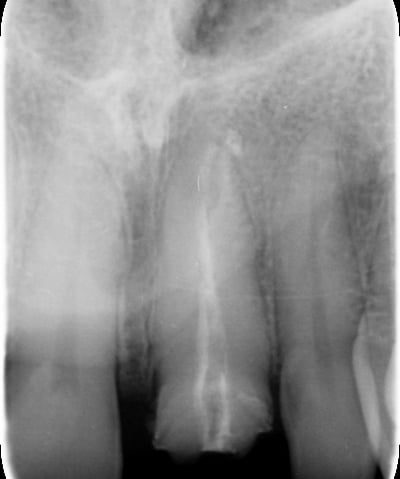

2. Sostituzione del perno moncone:

Una volta completato il trattamento canalare, è stato posizionato un nuovo perno in fibra di vetro. Questo materiale è stato scelto per la sua elasticità simile a quella della dentina, che riduce il rischio di fratture radicolari rispetto ai perni metallici tradizionali. Inoltre, la fibra di vetro è radiotrasparente, permettendo un migliore monitoraggio radiografico.